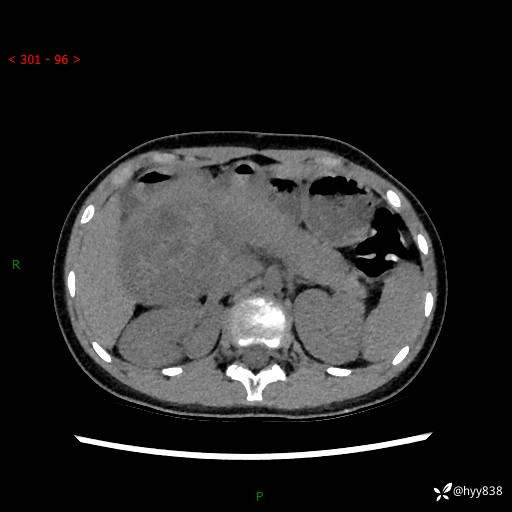

病例小姑娘,超声提示上腹部巨大包块。平扫就能轻松搞定的病变--结果公布

性别:女

年龄:13岁

简要病史:超声提示上腹部巨大包块

上腹部CT平扫

胰腺实性假乳头状瘤 (17)